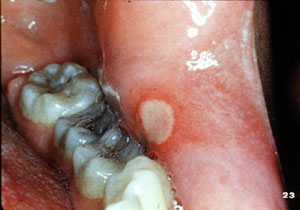

| Esta imagen

muestra una úlcera aftósica en curación, caracterizada por la

re-epitelización de la periferia.

Las úlceras

se desarrollan frecuentemente por tratamiento dental, varios tipos de

comida, trauma, medicamentos,

etc.